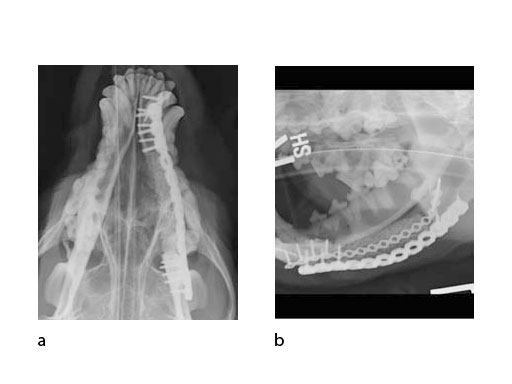

A block of compressive resistant matrix (CRM) was cut to fill this bone void, which was soaked with 2 mg of rhBMP-2. Fig 4 shows an intraoperative view of the 2 plates secured to the mandible and the CRM in place within the bone defect. The soft tissues were closed routinely. Immediate postoperative x-rays show the fixation (ventrodorsal view and lateral oblique view) (Fig 5). The radiopaque CRM can be observed spanning the 5 cm defect.